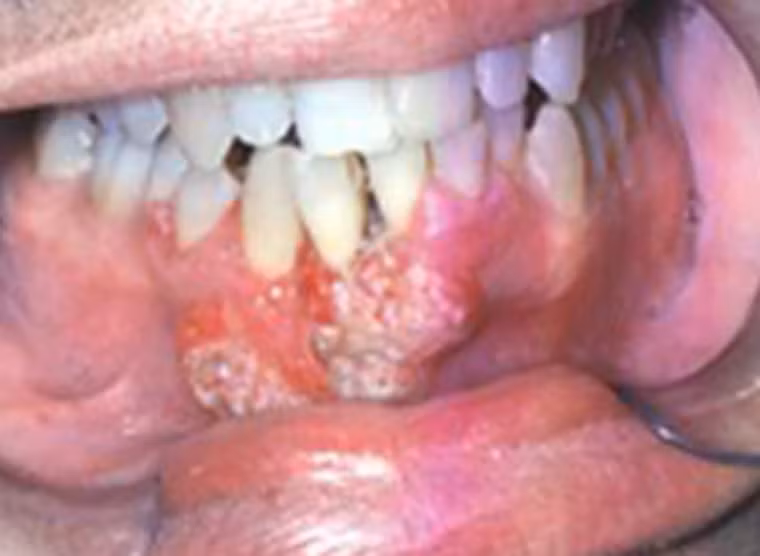

Còn đây là trường hợp của một bệnh nhân 55 tuổi, phần nướu bị tấn công bởi những khối u sần nhỏ, nó mở rộng phạm vi nhanh chóng, đặc biệt là khu vực môi dưới.